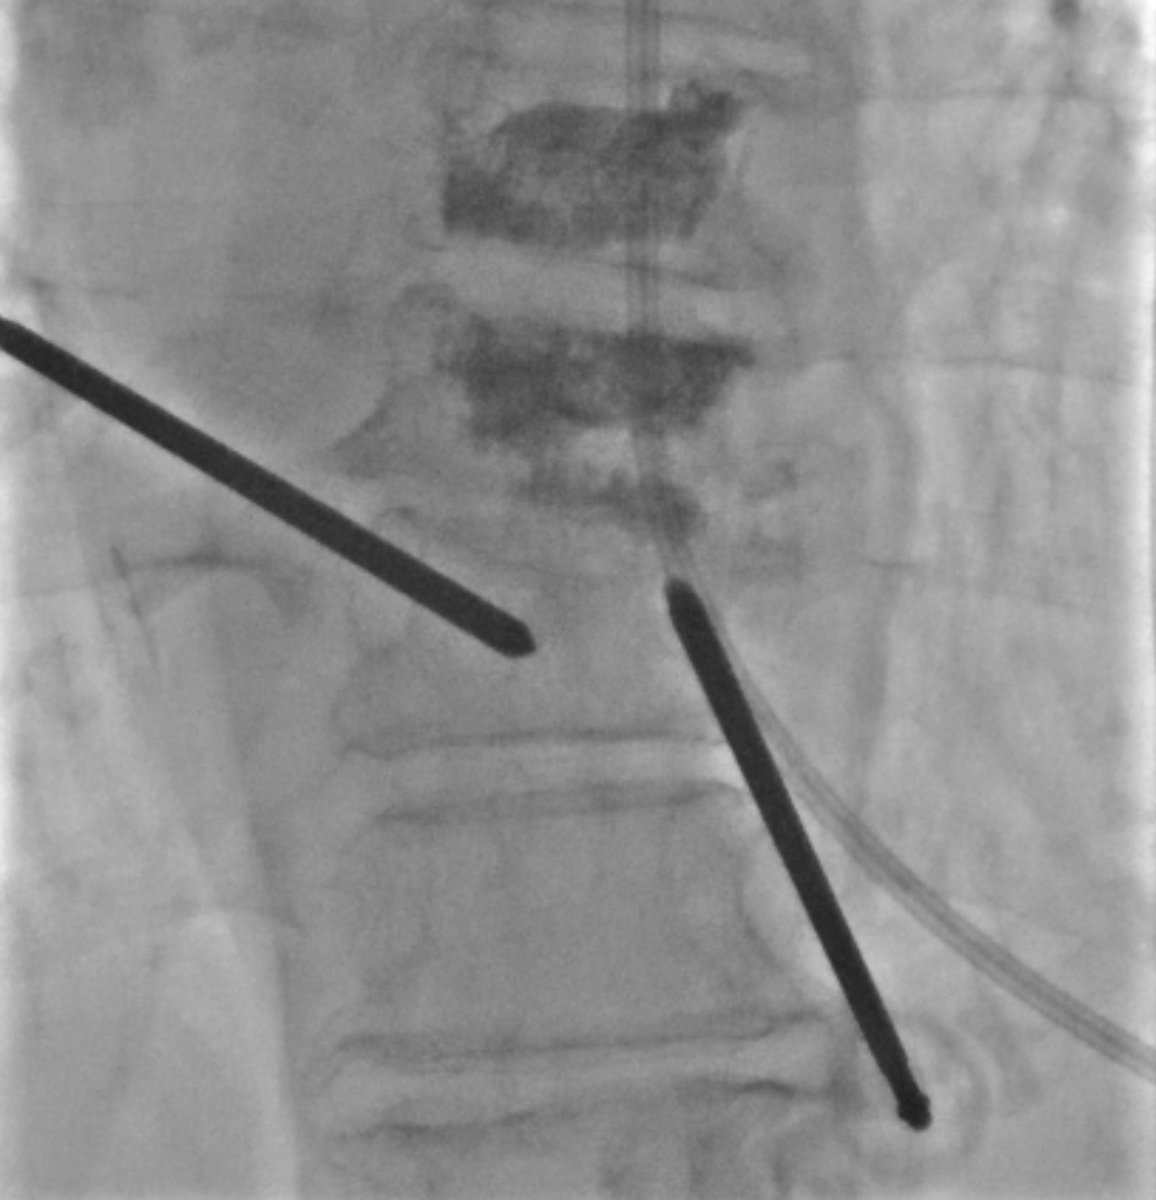

(1/) Left parapedicular/costovertebral access to center of T10, right transpedicular access with cranial trajectory to T9-10 disc space and T9 inf endplate. T10 balloon faced pressure from the sclerotic but unhealed endplate.

(3/) After initial cement from these accesses, the air filled fracture clefts are filled, but right side T10 is bare. Osteophyte blob = 👍🏼 Old accesses removed, new right transpedicular access with standard craniocaudal angulation. Moar curette. Curette = 🐐

(2/) Release the curette!

(4/4) A bit more cement and done. The main principle for treatment of hinge-fractures (DISH, ank spond) is stabilization, primarily from compressive forces. Cement from top of T9 to bottom of T10 accomplishes this. Close follow-up to ensure stability and tx add'l fractures.